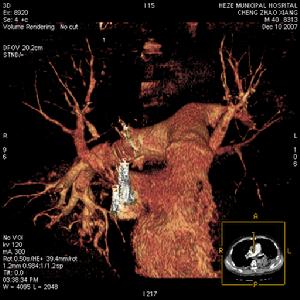

創傷愈嚴重,脂肪梗塞發生率愈高,症狀也愈嚴重,全身各臟器都可被侵犯。其中肺、腦、腎栓塞在臨床上比較重要。近來有些學者,鑒於脂肪栓塞往往發生於長期低血壓或休克的病人,因而認為脂肪球的產生,可能是由於肝臟的缺氧造成脂肪代謝的障礙所形成。

發生率約75%。開始於缺氧導致的呼吸急促及隨後的過度換氣,紫紺有時不會出現,但有時可能成為FES的早期體徵。涉及肺的FES病人大部分PaO2水平低於6.67kPa,如果肺的條件惡化,就可能合併呼吸困難和代謝性酸中毒。部分病人有咯血。胸部X線片示兩肺大塊斑片狀陰影,稱之為“暴風雪樣”改變,尤其在肺的上中部多見。